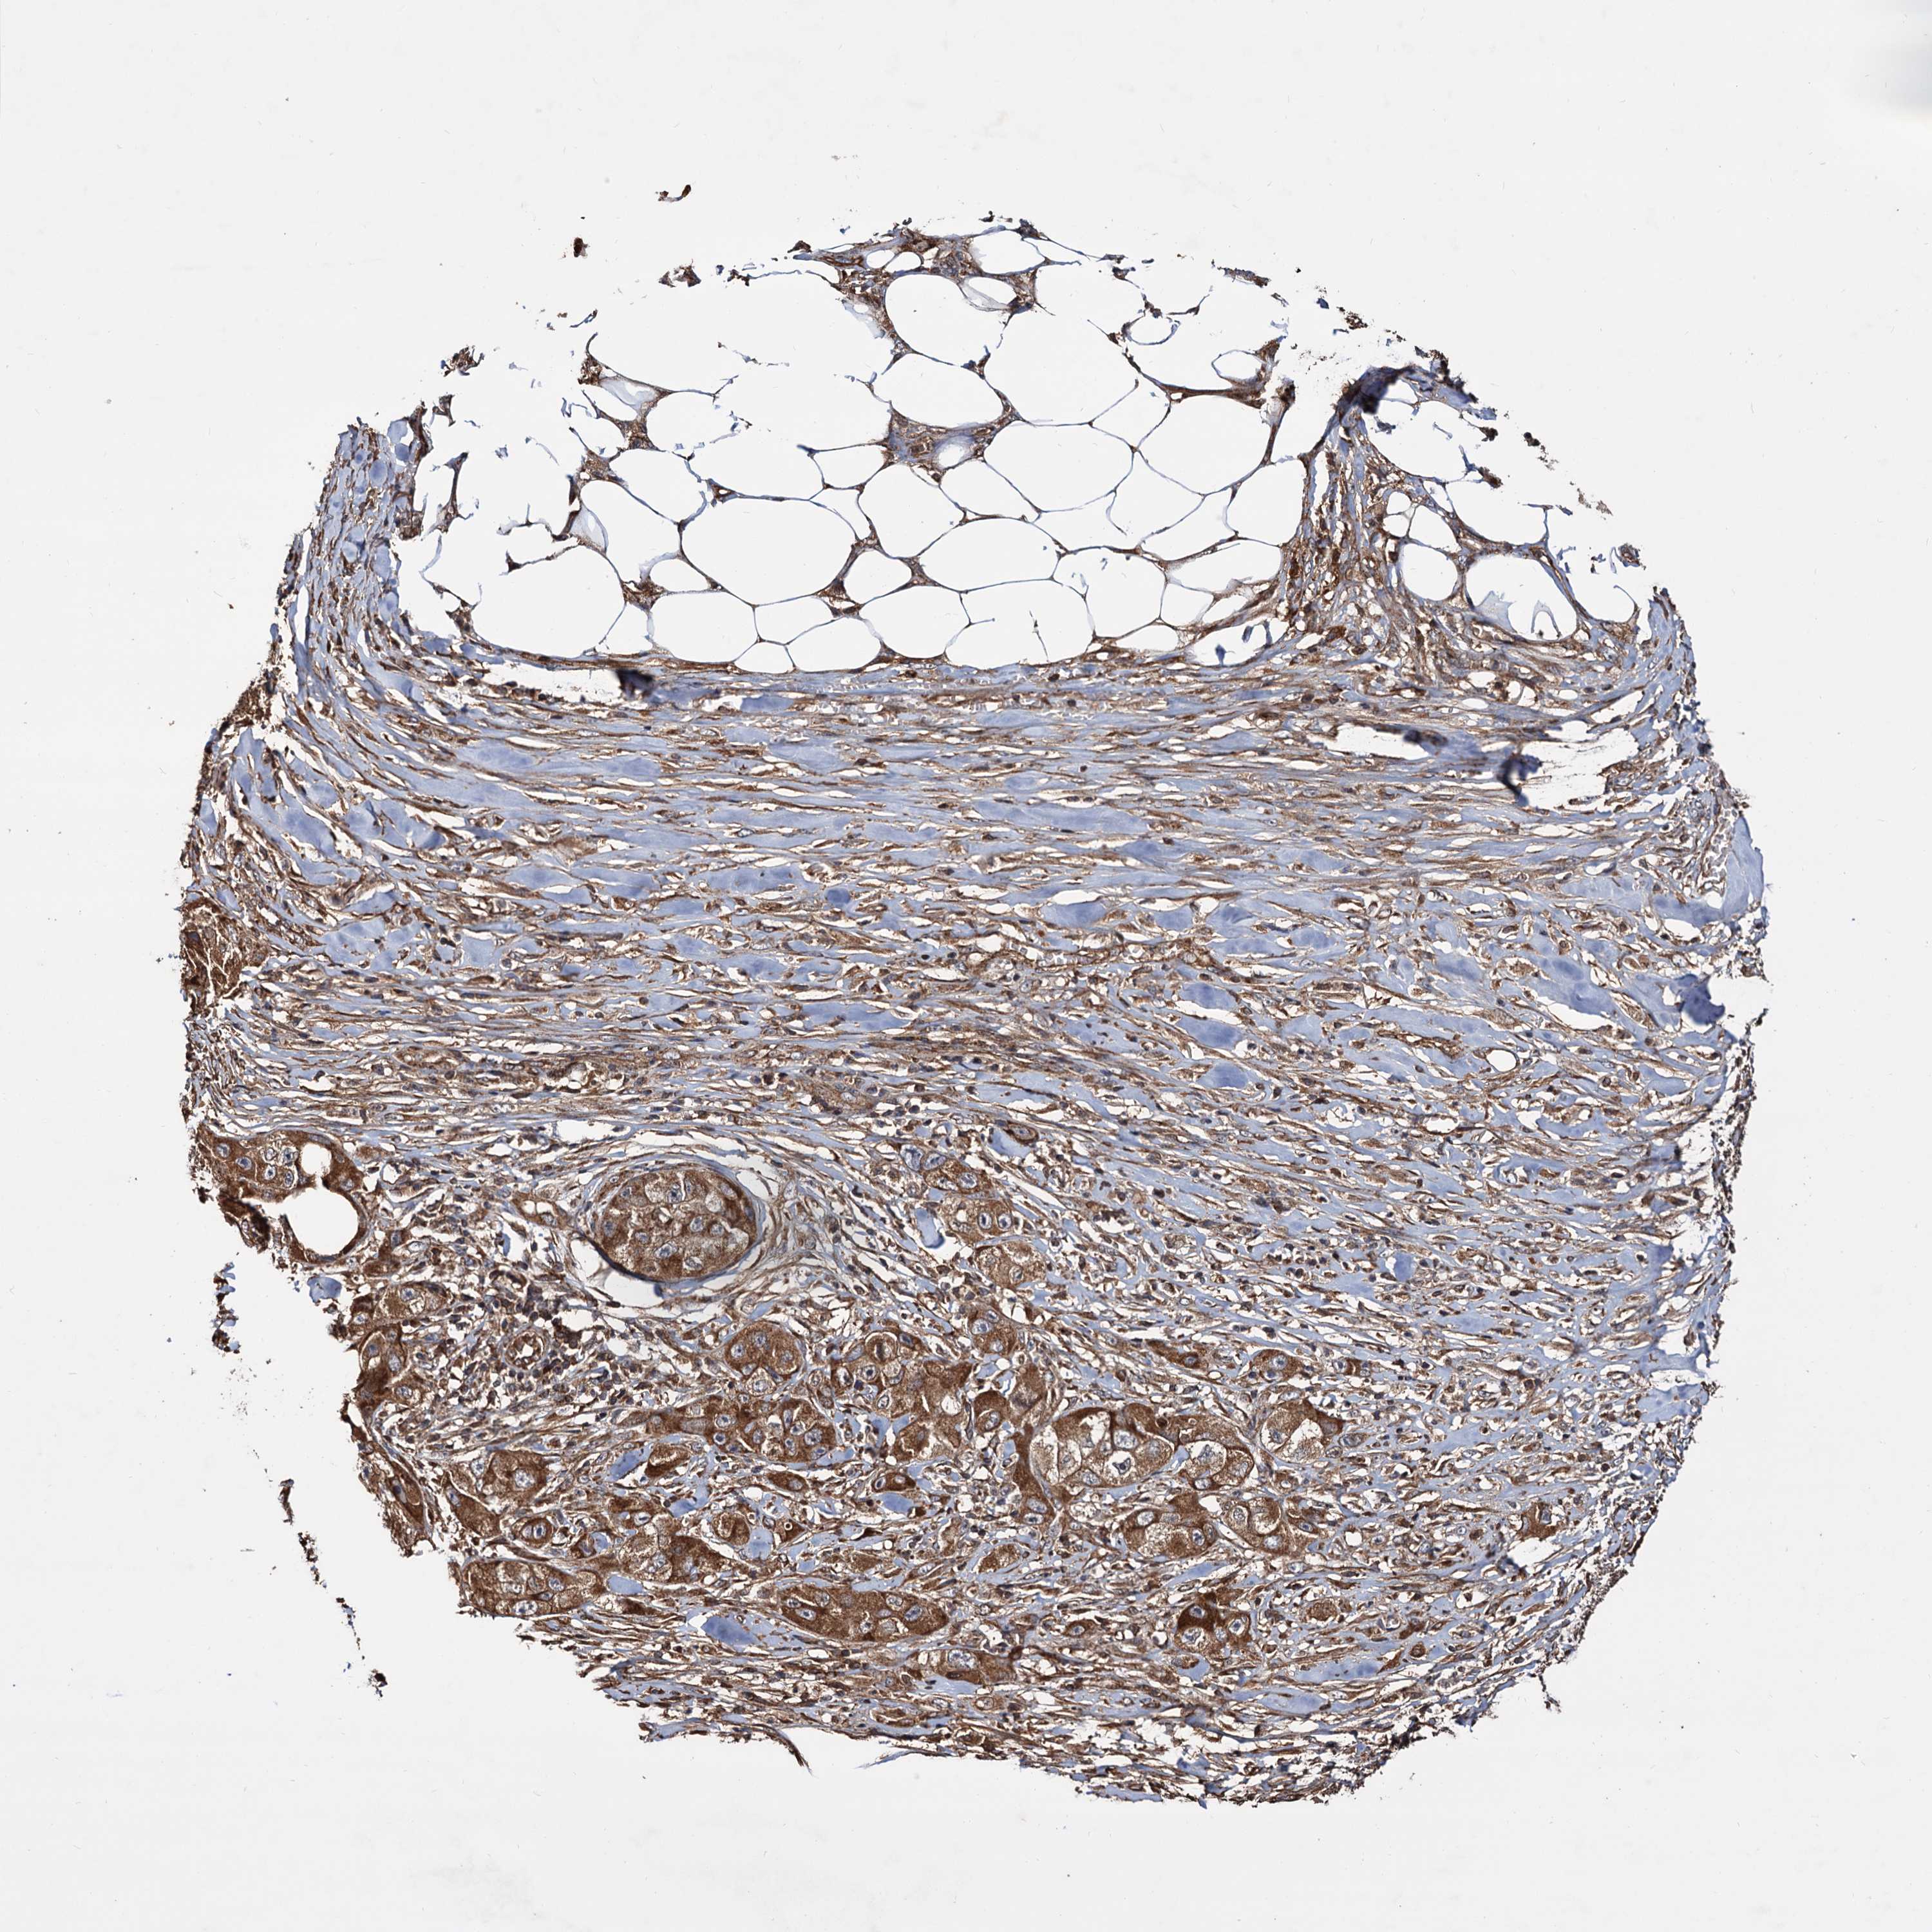

SKIN CANCER - Protein expressioni

A mouse-over function shows sample information and annotation data. Click on an image to view it in a full screen mode. Samples can be filtered based on level of antibody staining by selecting one or several of the following categories: high, medium, low and not detected. The assay and annotation is described here.

Antibody stainingi

Antibody staining in the annotated cell types in the current human tissue is reported as not detected, low, medium, or high, based on conventional immunohistochemistry profiling in selected tissues. This score is based on the combination of the staining intensity and fraction of stained cells.

Each image is clickable and will lead to virtual microscopy that enables deeper exploration of all samples and also displays staining intensity scores, fraction scores and subcellular localization as well as patient and tissue information for each sample.

Antibody HPA039398

Staining

High

Medium

Low

Not detected

Intensity

Strong

Moderate

Weak

Negative

Quantity

>75%

75%-25%

<25%

None

Location

Nuclear

Cytoplasmic/membranous

Cytoplasmic/membranous,nuclear

Squamous cell carcinoma, metastatic, NOS

Squamous cell carcinoma, NOS